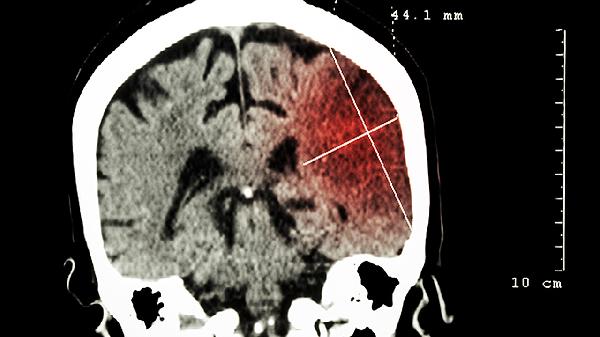

脑瘤早期症状主要有头痛、恶心呕吐、视力障碍、癫痫发作和肢体无力等。脑瘤是指颅内异常生长的肿瘤,可能压迫脑组织或神经,引发一系列症状。

肿瘤压迫视神经或视交叉可能导致视力下降、视野缺损或视物模糊。部分患者会感觉眼前有闪光或黑影,这种视觉异常通常呈进行性加重。定期眼科检查和头颅影像学筛查有助于早期发现病变。